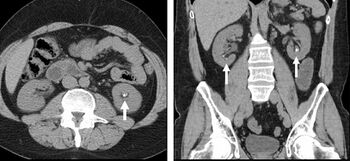

FIGURE 7. Selected images from a renal mass specific protocol CT. Corticomedullary phase (axial 7a) demonstrates peripheral enhancement of the renal cortex with minimal opacification of the renal medulla. There is a large renal cell carcinoma in the left kidney (right in image) which can be differentiated from the normal renal parenchyma by the heterogeneous and differential enhancement. The renal artery and vein are opacified in this phase as well. The collecting system is not opacified (coronal reformat 7b). In the parenchymal phase, the renal cortex and the medulla are enhancing. The renal cell carcinoma in the left kidney is not as well defined when compared to the corticomedullary phase images, but is actually slightly more conspicuous. There is some contrast noted within the collecting system during this phase (7c).[citation needed]